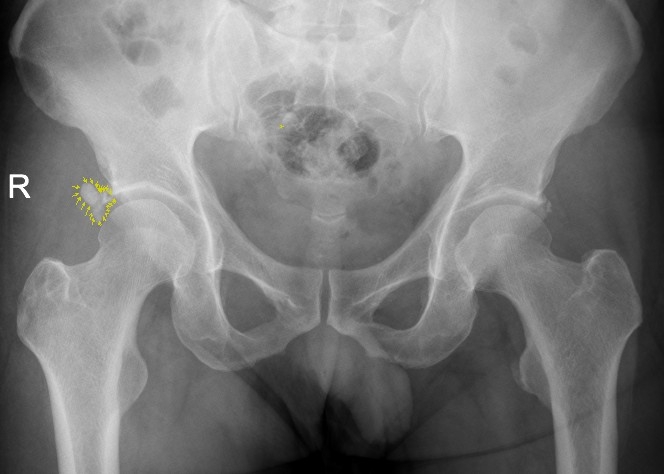

該患者為男性患者,47歲。右髖部疼痛7個(gè)多月,曾斷續(xù)就醫(yī),未明確診斷,疼痛時(shí)緩時(shí)重。入院前兩天,右髖部劇烈疼痛,患髖不能伸直,只能左側(cè)臥位,謂之“坐臥不寧”,需家人攙扶下才能勉強(qiáng)行走。經(jīng)臨床經(jīng)驗(yàn)豐富的骨三科主任、主任中醫(yī)師李彬以“右髖關(guān)節(jié)盂唇病變”收入住院治療,經(jīng)X光核磁共振檢查,患者右髖關(guān)節(jié)盂唇鈣化。

X片顯示盂唇鈣化病灶